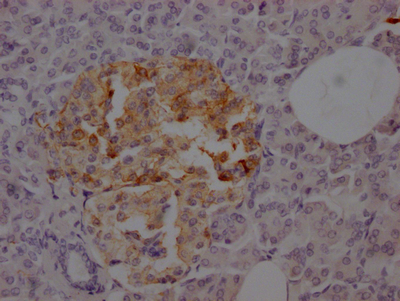

IHC image of CSB-RA827375A0HU diluted at 1:100 and staining in paraffin-embedded human pancreatic tissue performed on a Leica BondTM system. After dewaxing and hydration, antigen retrieval was mediated by high pressure in a citrate buffer (pH 6.0). Section was blocked with 10% normal goat serum 30min at RT. Then primary antibody (1% BSA) was incubated at 4℃ overnight. The primary is detected by a Goat anti-rabbit IgG polymer labeled by HRP and visualized using 0.05% DAB.

產(chǎn)品描述:CSB-RA827375A0HU SSTR2重組單克隆抗體是針對生長抑素受體2型(Somatostatin Receptor Subtype 2, SSTR2)設(shè)計(jì)的高特異性科研試劑。SSTR2作為G蛋白偶聯(lián)受體家族成員,廣泛參與調(diào)控激素分泌、細(xì)胞增殖及信號轉(zhuǎn)導(dǎo),尤其在神經(jīng)內(nèi)分泌腫瘤、垂體瘤等病理組織中呈現(xiàn)高表達(dá)特性,是相關(guān)疾病機(jī)制研究的重要靶點(diǎn)。本產(chǎn)品經(jīng)ELISA和免疫組化(IHC)嚴(yán)格驗(yàn)證,在IHC應(yīng)用中推薦使用1:50-1:200稀釋度,可清晰檢測石蠟包埋組織切片中的SSTR2蛋白定位,呈現(xiàn)高信噪比與低背景染色效果。抗體采用重組表達(dá)技術(shù)制備,具有優(yōu)異的批間一致性和穩(wěn)定性,適用于神經(jīng)內(nèi)分泌系統(tǒng)疾病模型研究、腫瘤標(biāo)志物表達(dá)分析以及激素調(diào)控相關(guān)信號通路探索等科研場景。研究者可借助該抗體在細(xì)胞或組織水平精準(zhǔn)解析SSTR2的分布模式及功能機(jī)制,為靶向治療基礎(chǔ)研究提供可靠工具。

應(yīng)用范圍:ELISA, IHC

Application Recommended Dilution IHC 1:50-1:200 -